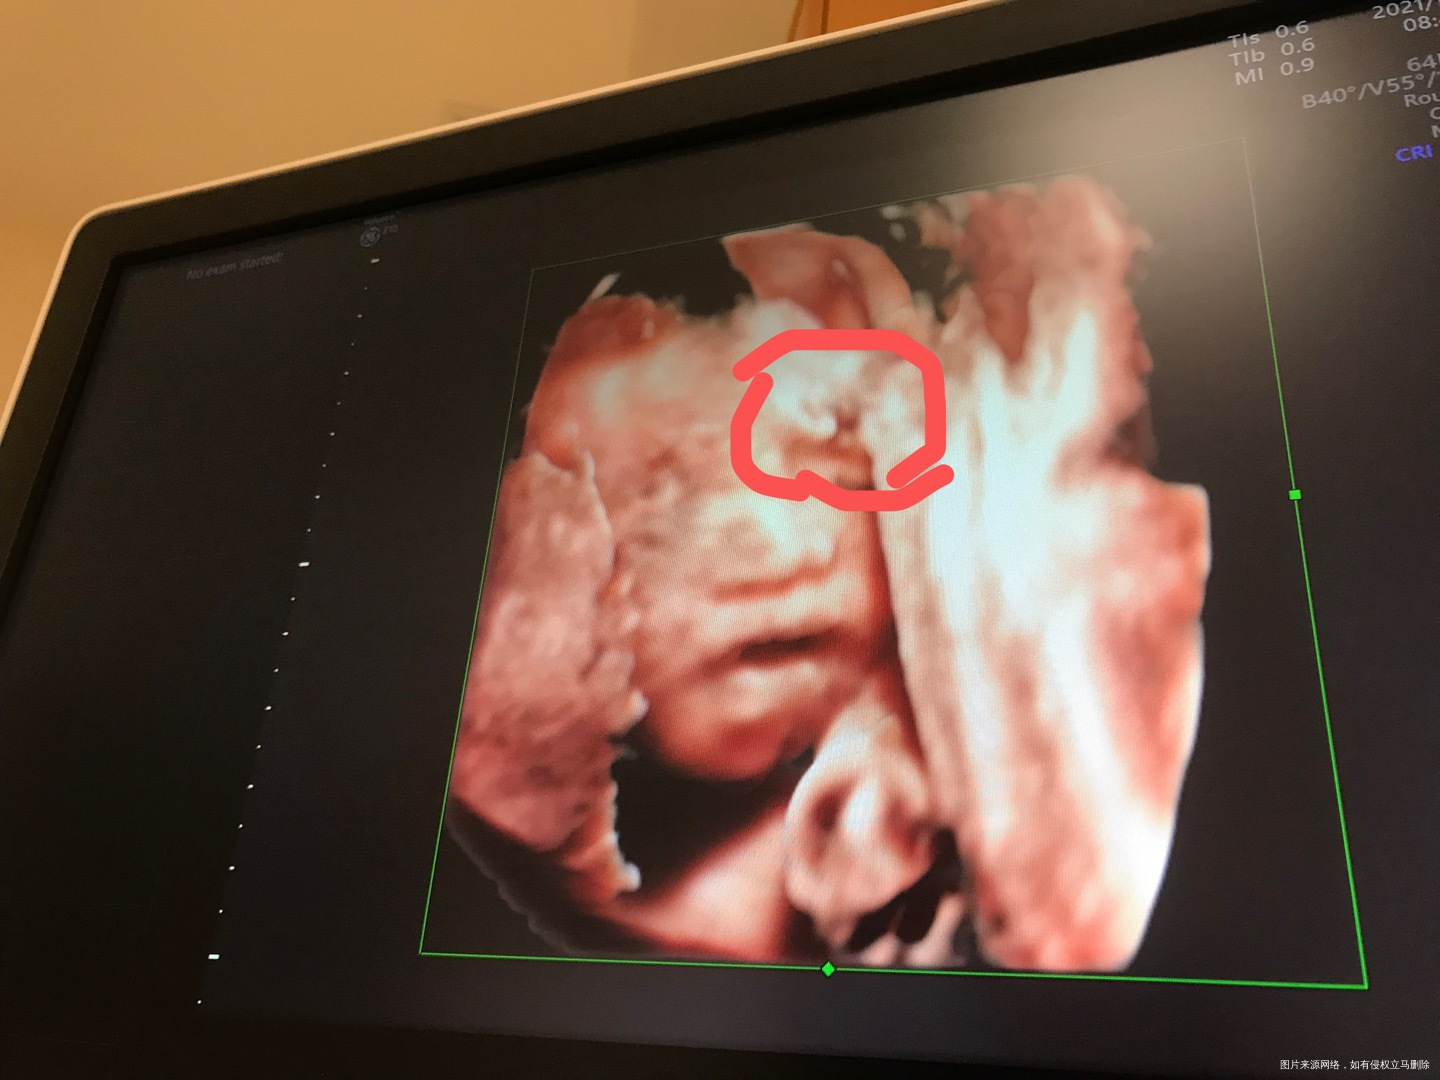

宝宝头上这是啥?四维彩超医生说正常的

看四维彩超要动态看,这样定格的是瞬间,可能是别的部位一起拍下来了,那个地方是额头,没有什么的,异常超声医生肯定回会报的。